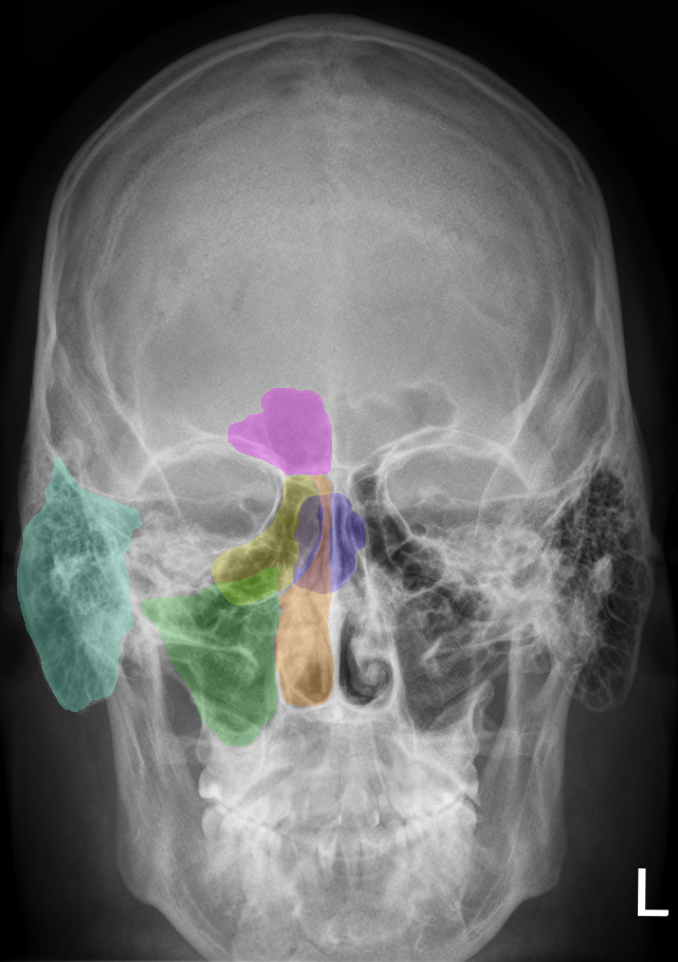

Middle Ear

Image taken from US Department of OSHA website

The Middle Ear refers to a collection of bones (ossicles) and muscles contained within a chamber (tympanic cavity) that sit between the Outer Ear and the Inner Ear, bounded by the tympanic membrane (eardrum) and the oval window respectively. The eardrum transforms air pressure waves into physical vibrations – the middle ear amplifies these vibrations – the oval window allows the amplified vibrations to “flow” into the fluid-filled cochlea. Therefore, the primary function of the middle ear is to act as a mechanical amplifier. Without the middle ear 99.9% of the sound energy entering the outer ear, and vibrating the eardrum, would be reflected by the fluid-filled inner ear. This is because fluid has a much higher impedance to sound waves than air, which in contrast is a very efficient medium.